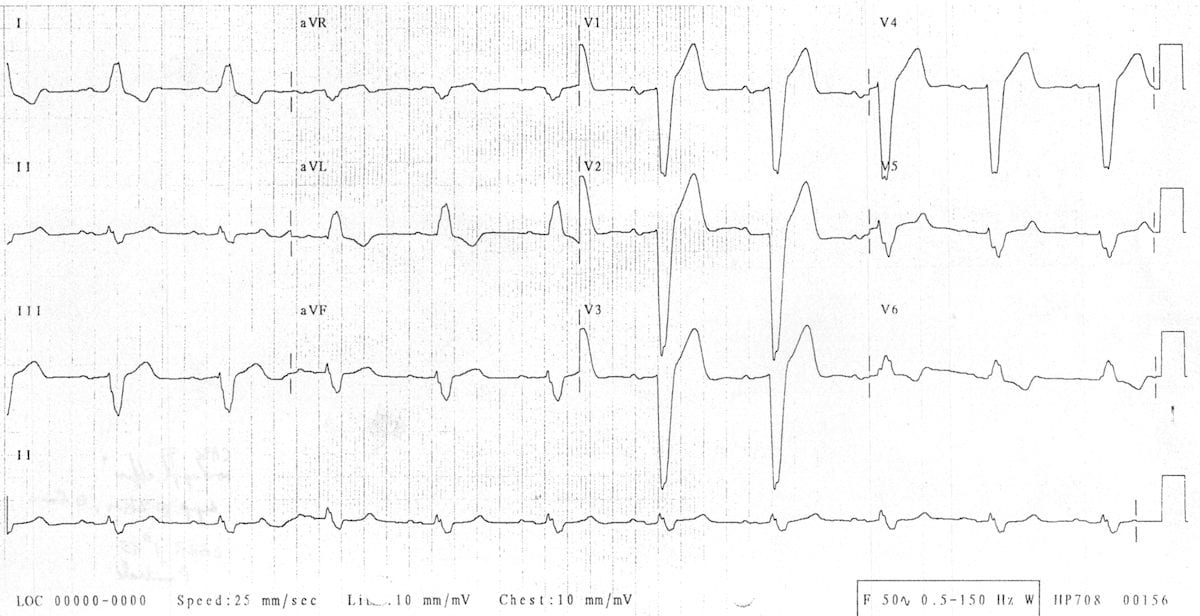

This ECG shows left axis deviation. Applying the thumb rule: lead I is up (+ve) and lead aVF is down (-ve). The left axis deviation is secondary to left ventricular hypertrophy.

© Life in the Fast Lane. Licensed under CC BY-NC 4.0

This ECG shows right axis deviation. Applying the thumb rule: lead I is down (-ve) and lead aVF is up (+ve). The right axis deviation is secondary to right ventricular hypertrophy (from cor pulmonale).

https://litfl.com/top-100-ecg-cases/

© Life in the Fast Lane. Licensed under CC BY-NC 4.0